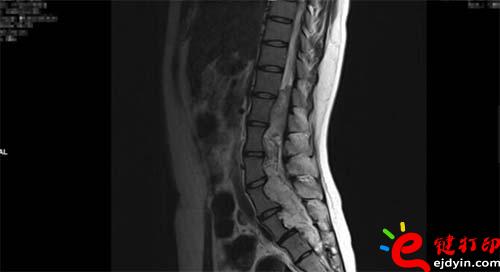

【VR和3D打印在微創(chuàng)椎管內(nèi)硬膜下先天性腫瘤切除術(shù)中的應(yīng)用】近日,山西省人民醫(yī)院成功完成一例微創(chuàng)通道胸12-骶2椎管內(nèi)硬膜下先天性腫瘤切除術(shù)手術(shù),在手術(shù)前醫(yī)院使用了西安鑫威泰科技自主研發(fā)的傲視虛擬現(xiàn)實數(shù)字醫(yī)療系統(tǒng)和3D打印模型進(jìn)行手術(shù)規(guī)劃,制定手術(shù)方案,對本次手術(shù)的成功起到了至關(guān)重要的作用。